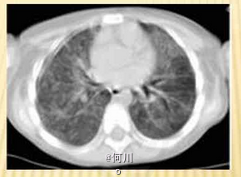

流涕、轻咳、低热、纳差 辅查胸片,X线表现为两肺纹理增粗、增多,模糊。CT可见双肺沿支气管分布的大片状模糊影